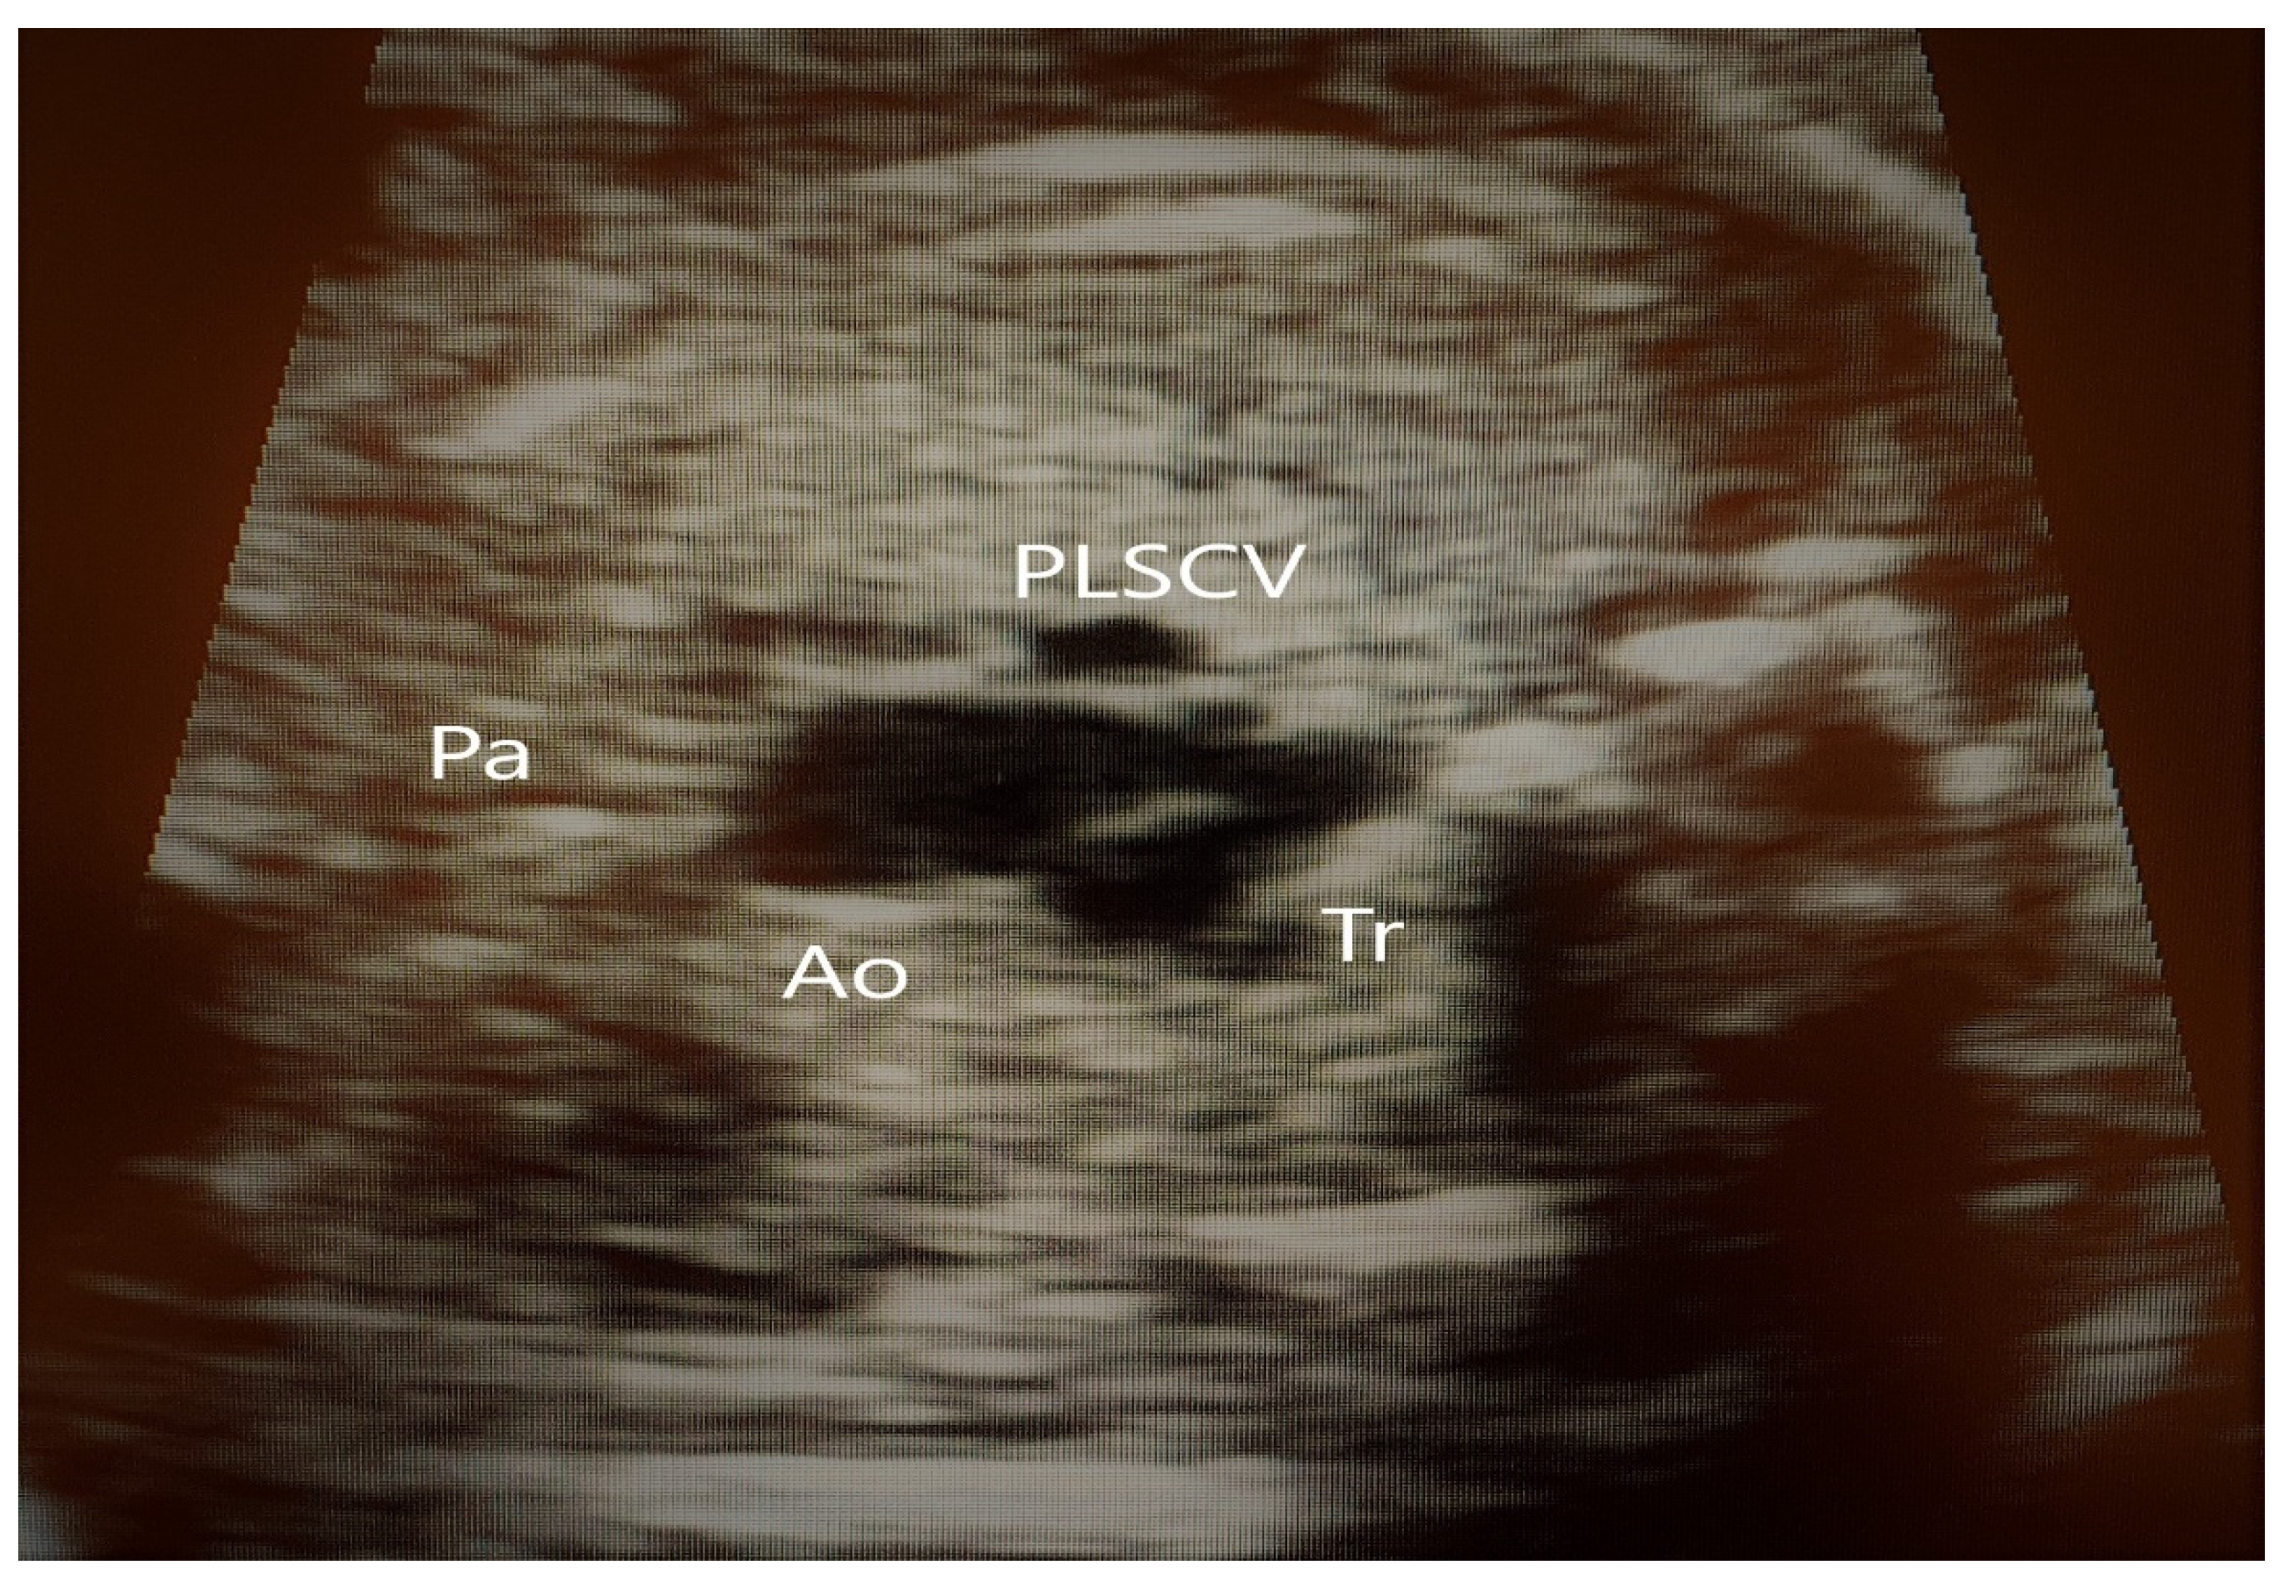

4. Cases—Ultrasound Findings Description

4.1. Case 1

4.2. Case 2

4.3. Case 3

4.4. Case 4